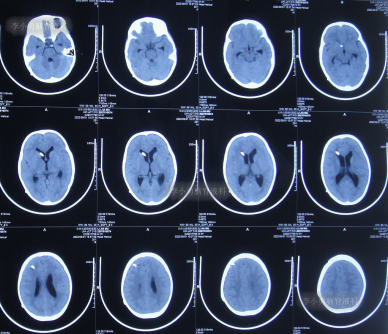

第3家医院治疗16天即2022年6月9日,不但依然发热,而且查头颅CT示脑室稍扩张(图-3)。

图-3:2022年6月9日头颅核磁